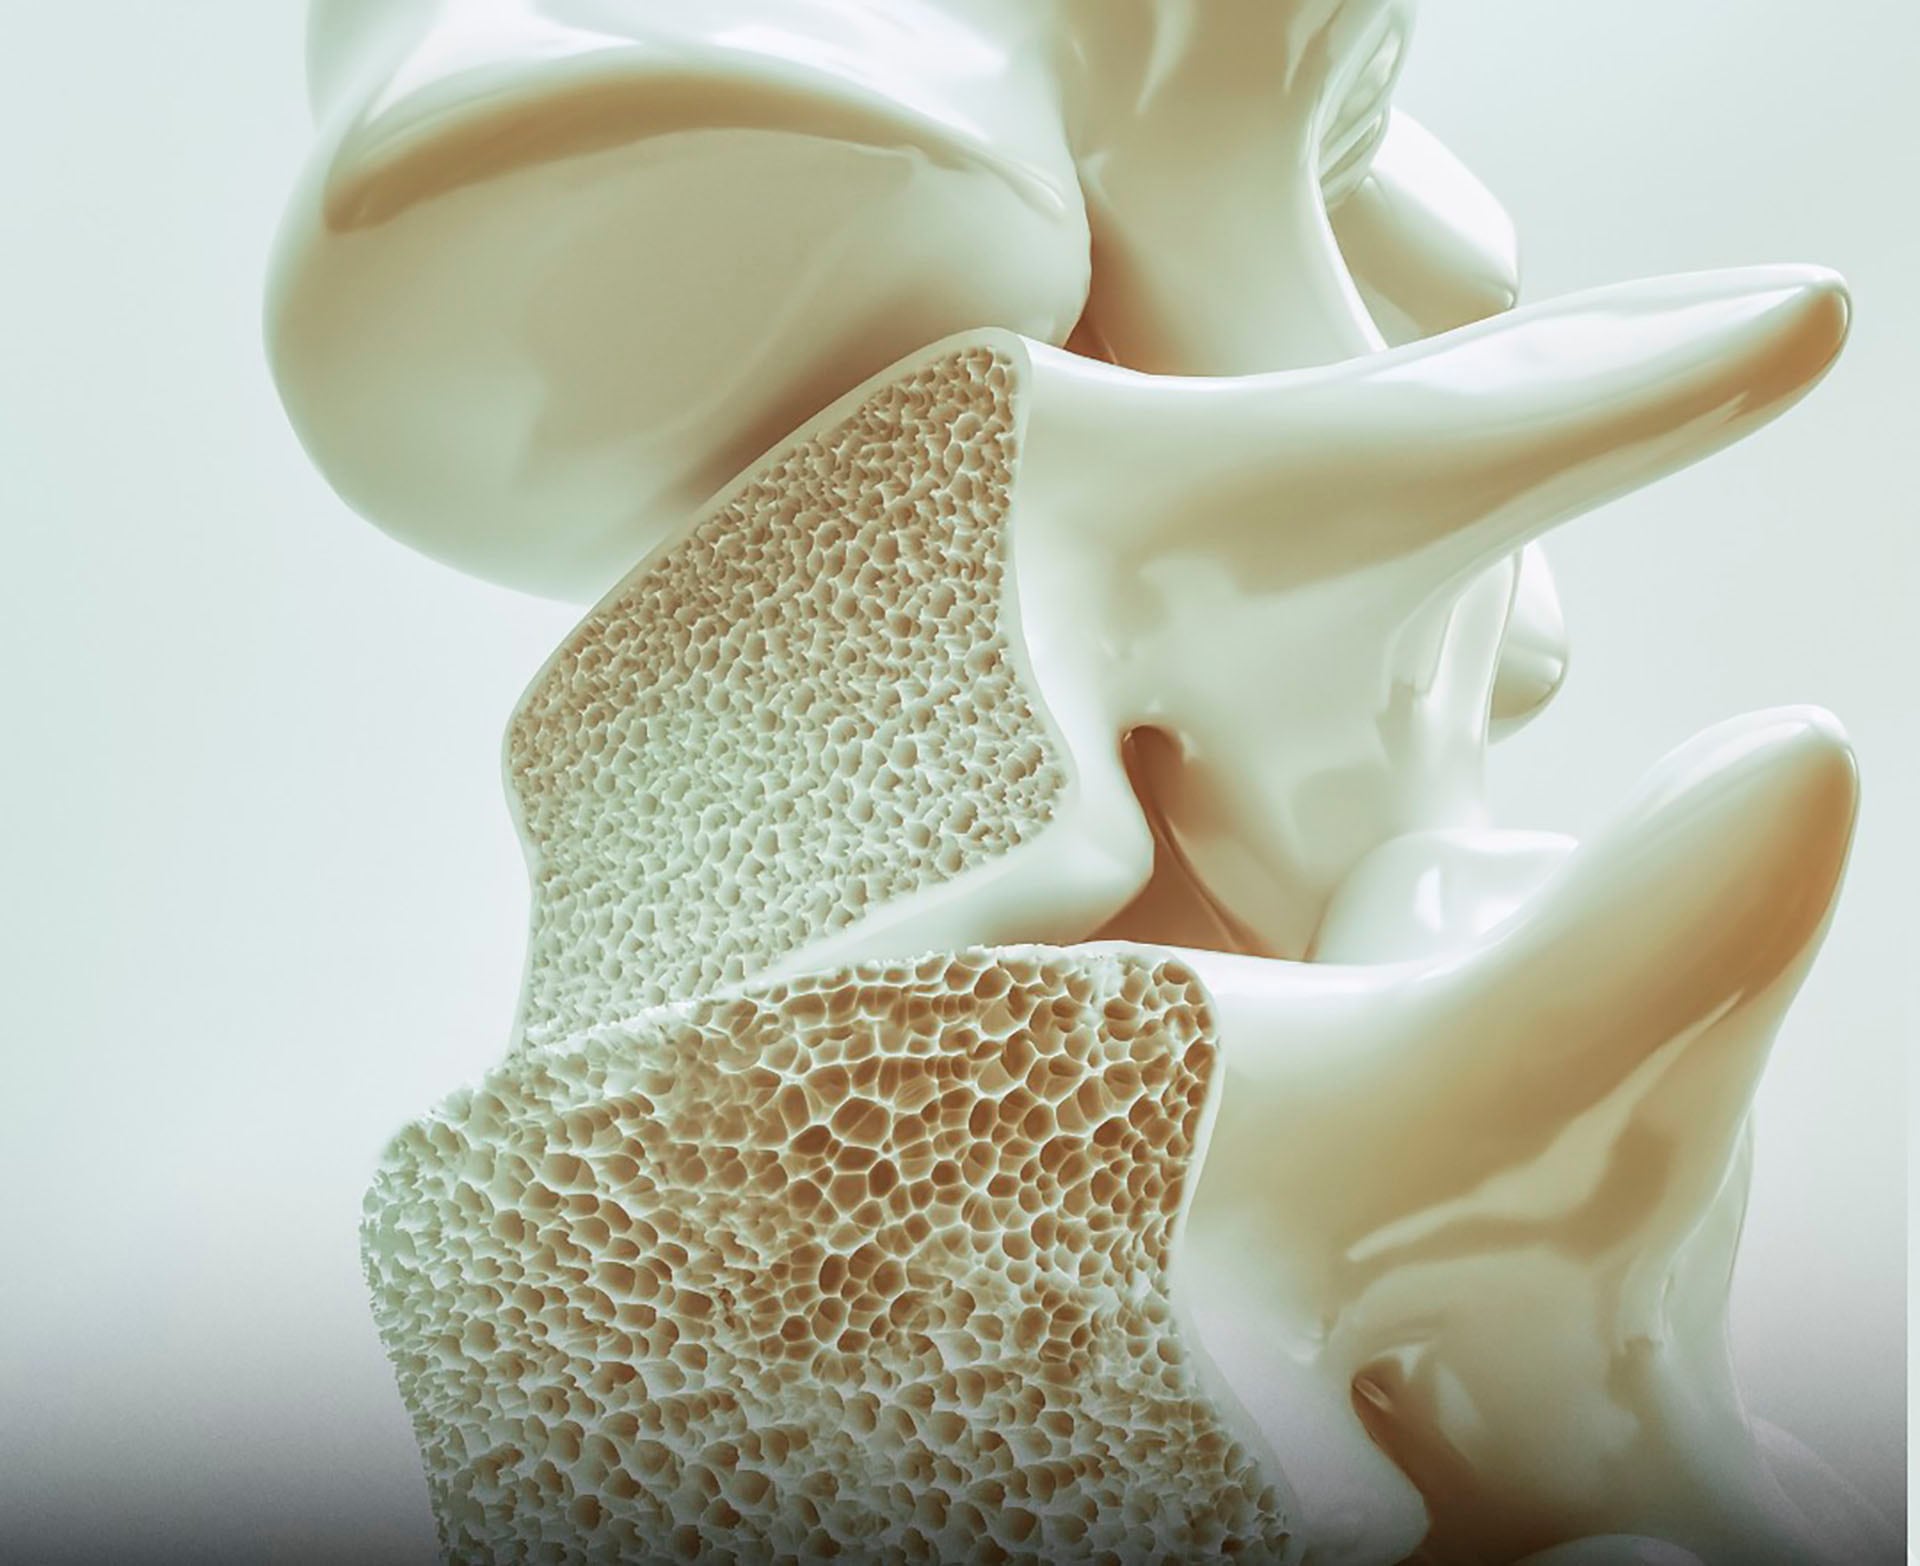

Osteoporosis: una epidemia silenciosa con impacto global

La osteoporosis representa una preocupación creciente de salud pública a escala mundial, con millones de personas afectadas y más de dos millones de fracturas atribuidas a esta enfermedad cada año, según la Harvard Medical School.

Las fracturas de cadera son especialmente alarmantes, ya que seis de cada diez personas que se fracturan la cadera nunca recuperan por completo su nivel anterior de independencia. Esta pérdida de autonomía afecta significativamente la calidad de vida y eleva los costos sanitarios.

¿Por qué se debilitan los huesos con la edad?

El impacto de la osteoporosis se intensifica con el envejecimiento. A partir de los 40 años, la inactividad física y una alimentación insuficiente en calcio y vitamina D generan una pérdida anual de masa ósea cercana al 1%, alerta la Harvard Medical School.

Los huesos de la cadera, la columna vertebral y las muñecas —los más propensos a fracturas— son los que más se benefician de la estimulación mecánica del ejercicio. Esta fragilidad ósea también se ve agravada por factores hormonales, como la disminución de estrógenos en las mujeres postmenopáusicas, y por condiciones crónicas como la diabetes o el uso prolongado de corticoides.

Al aplicar cargas controladas mediante rutinas de resistencia, se estimula la actividad de los osteoblastos, las células responsables de regenerar el tejido óseo. Este proceso de remodelación es fundamental para mantener huesos fuertes y flexibles ante impactos o caídas.